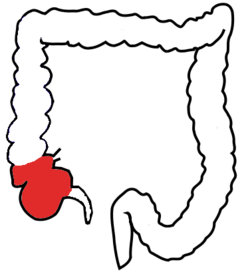

Cecum

Vermiform appendix

Ascending/transverse/descending/sigmoid colon

Anus

Ileocecal valve